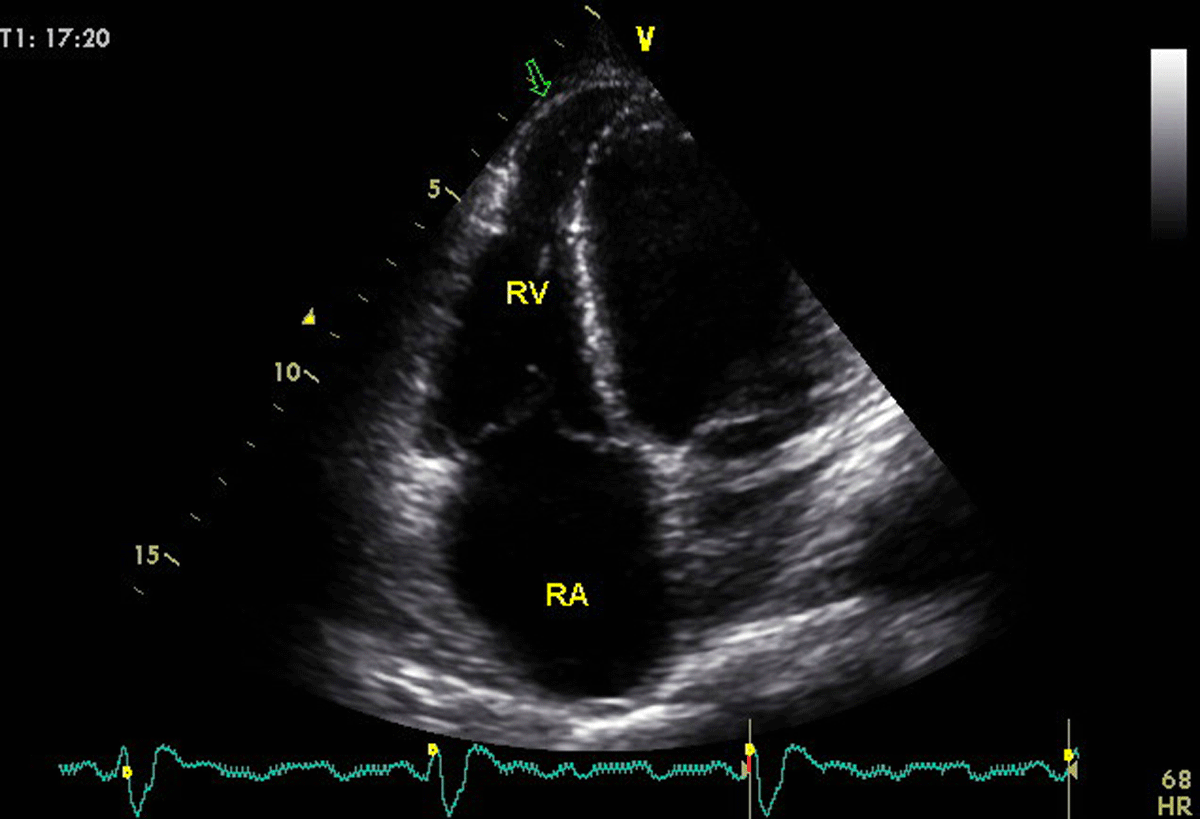

Figure 4

A young patient with Chagas disease presenting with biventricular dysfunction. Arrow in the 4 chamber-view, optimized to visualize the right ventricle, shows the infrequent finding of right ventricular aneurysm. Image: Marcia Barbosa. Reproduced with permission of the photographer.